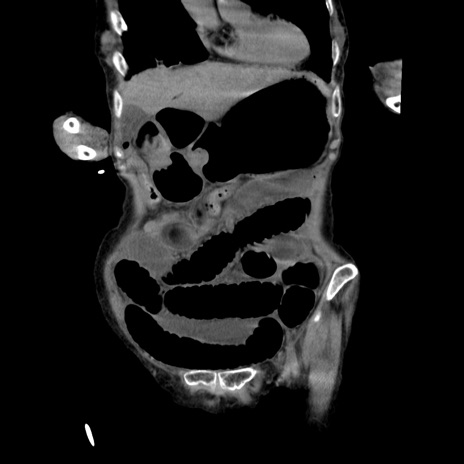

横断像

【症例】80歳代女性

【主訴】嘔吐、腹痛

【現病歴】数時間前より嘔吐あり。心窩部痛出現し、徐々に右下腹痛あり。その後も数回嘔吐あり救急搬送となる。

【既往歴】左大腿骨頚部骨折手術

【身体所見】腹部は膨隆しているが軟らかく圧痛なし。腸雑音はやや亢進。

【データ】WBC 12000、CRP 19.05